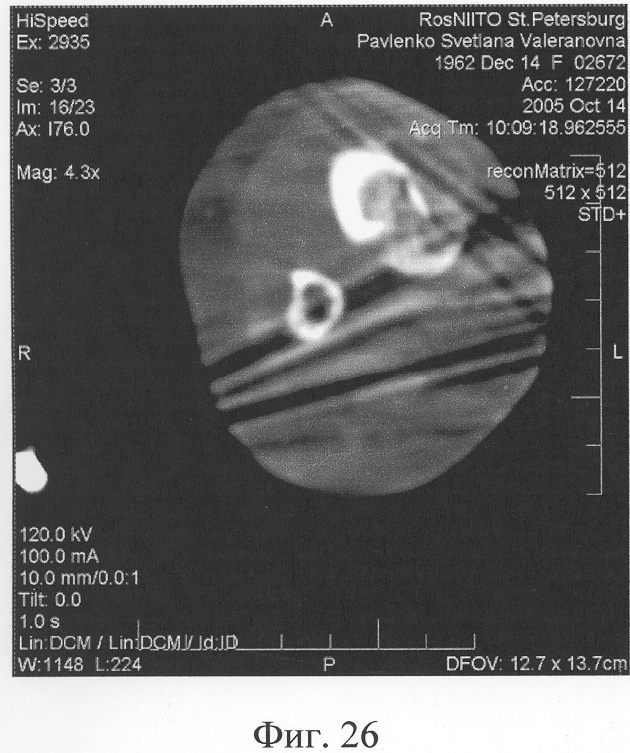

Аппарат внешней фиксации с левой голени демонтирован через 3 месяца после операции при клинико-рентгенологической картине сращения перелома. Аппарат внешней фиксации с правой голени демонтирован через 7 месяцев после операции при клинико-рентгенологической картине сращения перелома (фиг.20-25 – результат лечения). При рентгенологическом и томографическом контроле в трансплантатах отмечалось постепенное нарастание плотности костной ткани с формированием костной мозоли на всем протяжении между трансплантатом и костными фрагментами (фиг.26-29 – динамика данных компьютерной томографии правой голени: отмечается нарастание плотности костной ткани в области трансплантатов и формирование регенерата между смещенным трансплантатом и костными фрагментами; фиг.30-33 – динамика данных компьютерной томографии левой голени: отмечается нарастание плотности костной ткани в области трансплантатов и формирование регенерата между трансплантатом и костными фрагментами).